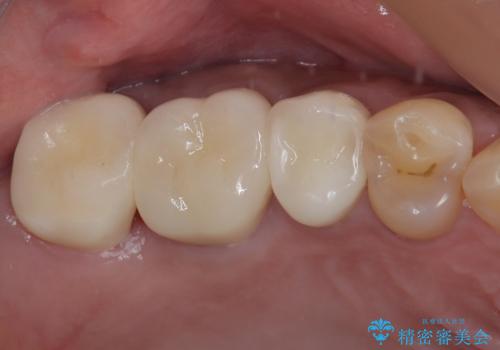

目立つ銀歯と欠けてしまった詰め物 オールセラミッククラウンでの補綴治療